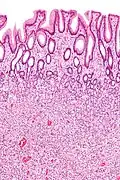

| Fundic gland polyp | Fundus of stomach | Cystically dilated glands lined by chief cells, parietal cells and mucinous foveolar cells.[15] | Very low or none, when sporadic.[16] | ![]() |

Fundic gland polyposis |